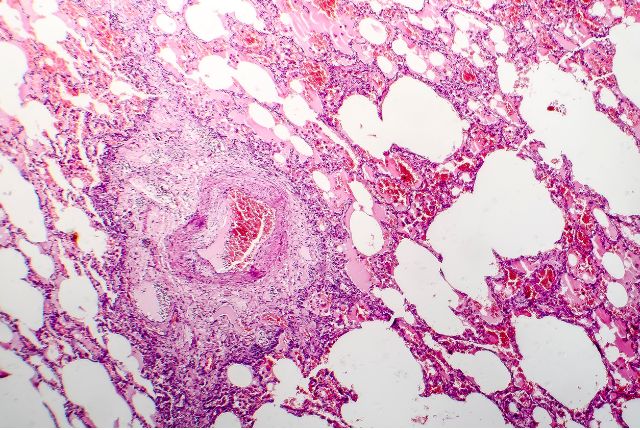

L’œdème du poumon, également appelé œdème pulmonaire, survient lorsque du plasma sanguin (la partie liquide du sang) traverse la paroi des capillaires pulmonaires vers les espaces interstitiels et les alvéoles.

En temps normal, le système circulatoire permet le passage de l’eau et des nutriments entre le sang et les tissus à travers les parois des capillaires. Ces échanges sont régulés par une pression hydrostatique, oncotique ou ionique. L’insuffisance cardiaque gauche engendre des problèmes de circulation. Le cœur perd ses capacités musculaires et ne peut plus assurer correctement les échanges nécessaires au bon fonctionnement de l’organisme. Résultat : le sang s’accumule dans la circulation pulmonaire et la pression de remplissage du ventricule gauche augmente brutalement, ce qui entraîne l’œdème pulmonaire.

- une radiographie du thorax qui met en évidence l’infiltration de plasma dans les alvéoles pulmonaires ;